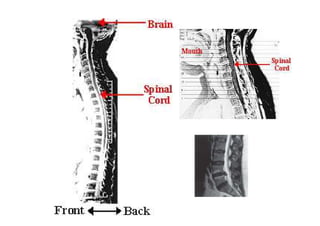

• 3. Ressonância Magnética

Opção preferencial para detecção de

patologias de partes moles tais como hérnia

de disco e tumores. Estudo realizado em 100

pacientes com doenças na laringe, sem

queixas clínicas relacionados à coluna cervical,

evidenciaram 20% de lesão discal em

pacientes entre 45-54 anos e 57% com mais de

64 anos.

07/12/2015 Dr. José Heitor M. Fernandes 76Neuroimagem